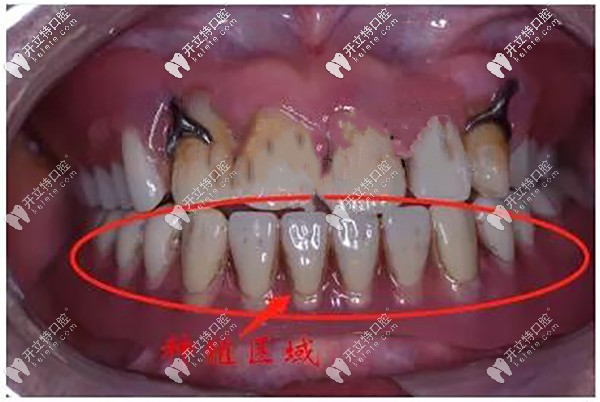

從上圖全醫(yī)生判斷:楊先生多年嚴(yán)峻慢性牙周炎,多數(shù)牙齒松動脫落,牙列缺損、殘根。

給出的治療方案:allon4種植下半口,即拔即種,殘根、松動牙拔除。

先給老人把口腔內(nèi)的牙齒遺 留的殘根、松動牙齒拔除掉▼

牙齒遺 留的殘根、松動牙齒拔除掉